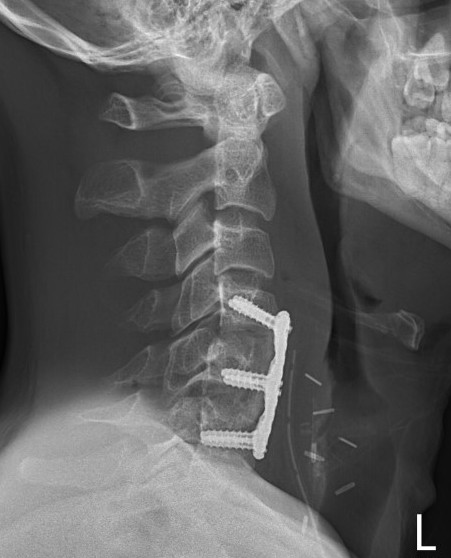

A. Anterior corpectomy & fusion with tricortical graft + plate

B. Anterior corpectomy & fusion with mesh cage + bone graft + plate

+/- Supplemental posterior fixation / cervical lateral mass screws

Anterior corpectomy and tricortical graft